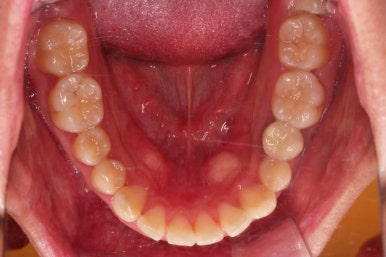

초진 시 입안의 모습입니다.

옆쪽에서 보면 치아와 치아가 1:1로 부딪히는데(화살표 표시) 좋지 못한 교합입니다.

윗니와 아랫니가 앞뒤로 지그재그 서로서로 껴있어야 좋은 교합인데 전반적으로 윗니가 앞으로 밀려있는 양상의 교합이에요.

장기적으로 치아, 잇몸 건강에 좋지 못하답니다.